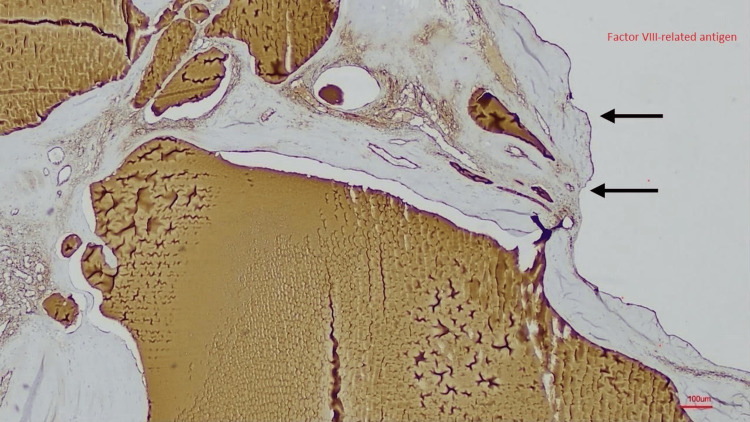

Splenic lymphangiomas, per se, are exceedingly rare, benign congenital malformations of lymphatic vessels, typically diagnosed in childhood or incidentally in adulthood. Appendiceal mucinous neoplasms (AMNs) are also infrequent, often asymptomatic, and usually discovered incidentally. To date, the co-occurrence of these two distinct primary lesions in the same patient has not been previously reported. We present the case of an 83-year-old Turkish female who underwent emergent abdominal surgery for an acute abdomen secondary to a strangulated left diaphragmatic herniation. Multiple perforations were identified in the transverse colon, accompanied by widespread ischemia involving the terminal ileum, cecum, and right colon. Upon laparotomy, a diaphragmatic defect measuring approximately 10 cm in diameter was identified in the left hemidiaphragm. The herniated abdominal viscera were meticulously reduced and examined, and multiple perforations were identified in the transverse colon, accompanied by widespread ischemia involving the terminal ileum, cecum, and right colon. An emergent splenectomy was performed due to severe ischemia and irreparable structural damage observed within the compromised hernia sac, with the resection of the terminal ileum, the ascending, and transverse colon. During the operative intervention, both a splenic lymphangioma and a low-grade AMN were incidentally discovered. The histological diagnosis was confirmed with factor VIII-related antigen (factor VIII-R antigen) immunohistochemical positivity. The patient, unfortunately, succumbed on the fifth postoperative day due to progressive multi-organ failure. This report documents the first known instance of the simultaneous identification of splenic lymphangioma and AMN as primary lesions in a single patient. This unique case underscores the critical importance for surgeons to remain vigilant for unexpected pathologies and highlights the necessity of a multidisciplinary approach in evaluating rare incidental findings for appropriate classification and follow-up.